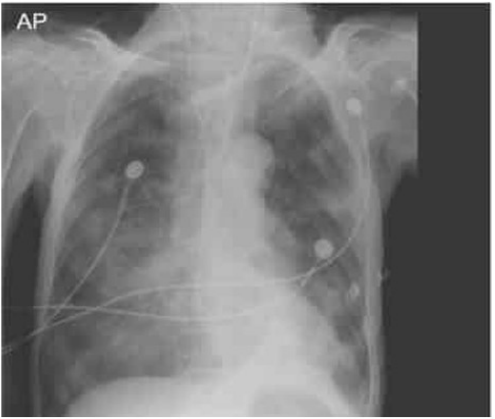

Paciente masculino, 70 anos, internado na UTI há 4 dias com acidente vascular cerebral isquêmico, apresentou episódio importante de aspiração alimentar. A radiografia de tórax foi solicitada e realizada cerca de 12h após o ocorrido, sendo observado o resultado com a imagem a seguir:

O quadro pulmonar apresentado é compatível com: